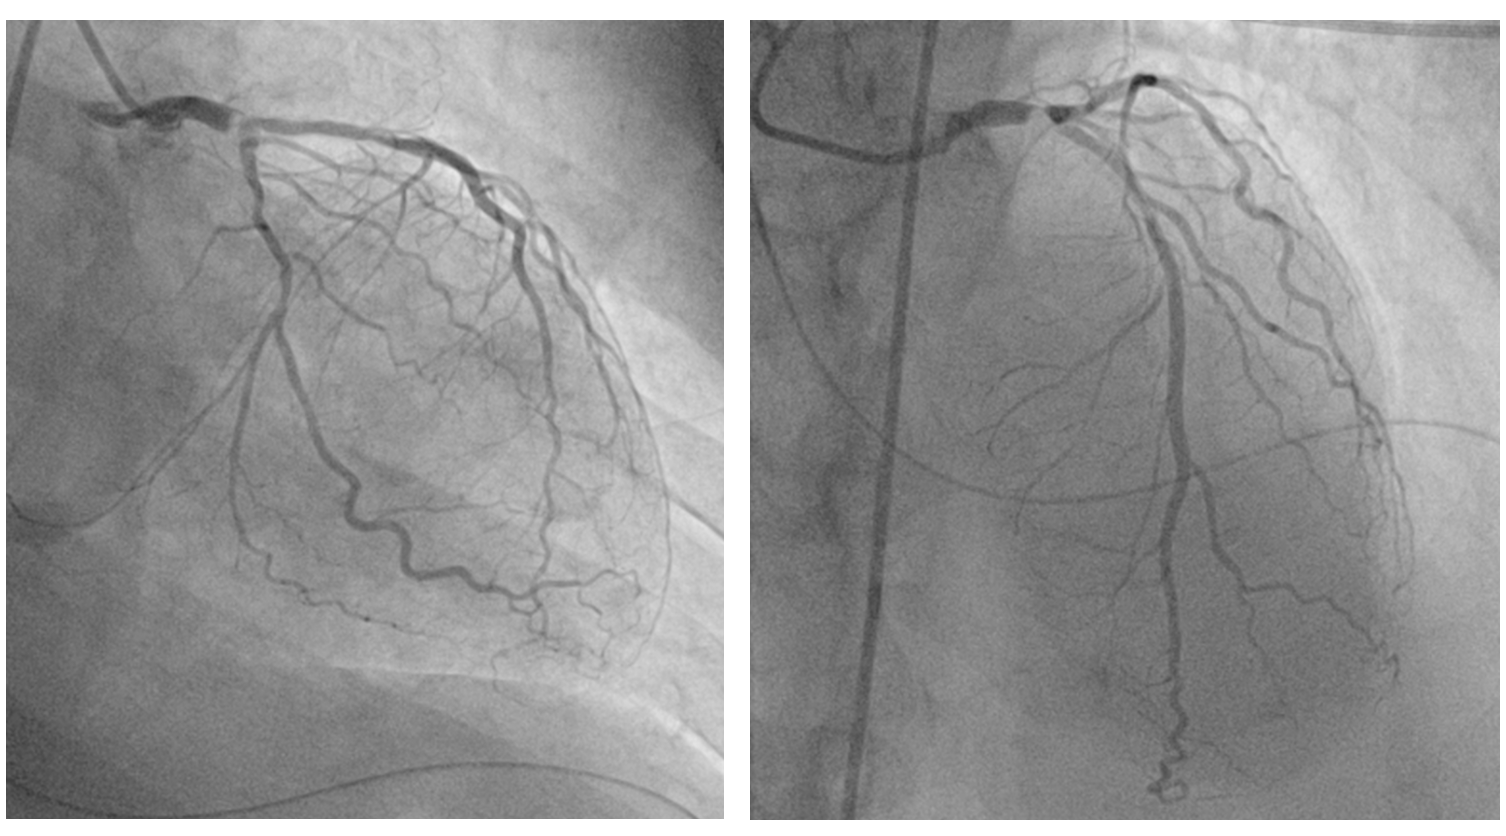

Due to a weak radial pulse, right femoral artery access was obtained for coronary angiography. A 6 French sheath was inserted. Angiography revealed : 95% stenosis with calcification of the distal left main coronary artery (LMCA), 70-80% stenosis of the proximal - mid left anterior descending artery (LAD), 50%-60% stenosis of the proximal left circumflex artery (LCx) and normal right coronary artery (RCA).